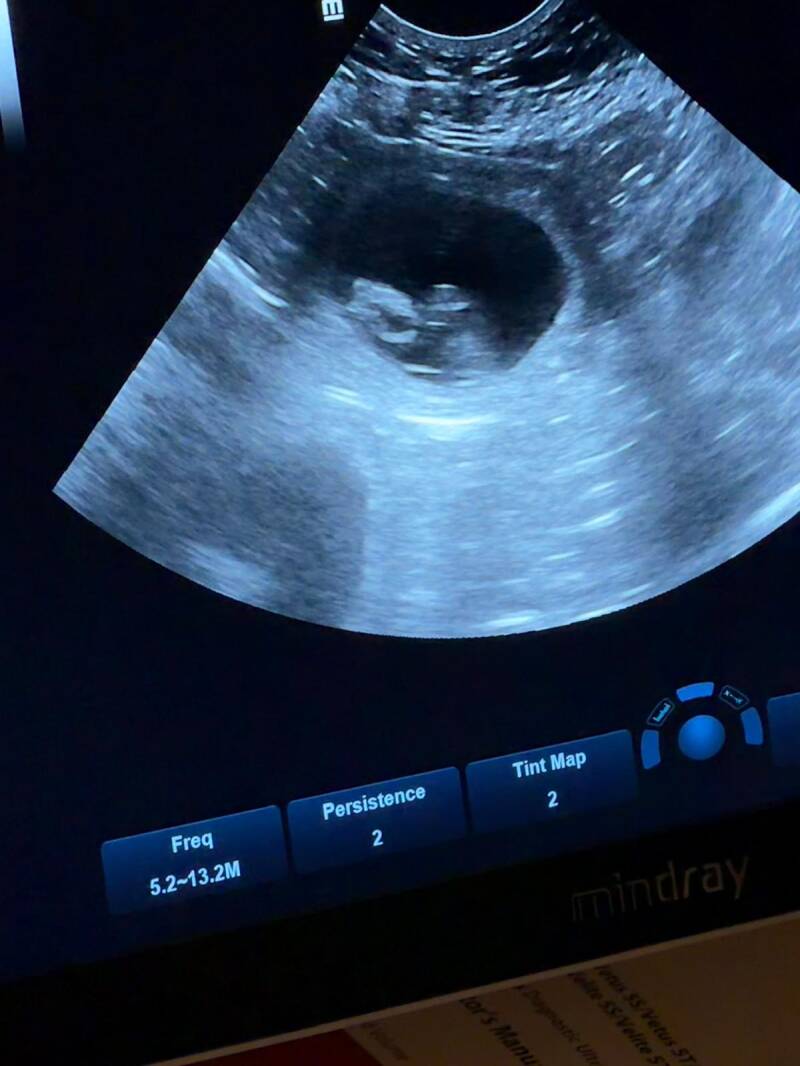

Ja hoor, het is bevestigd.....Azlynn is drachtig en op de echo hebben we al kunnen constateren dat ze een volle buik heeft!

PUPPYLOOK DRACHTECHO

Sandra en Pieter hebben een pup uit ons B-nest, een zusje van onze Birdy.

Sandra heeft vorig jaar haar droom verwezenlijkt om haar passie voor echografie te combineren met haar liefde voor dieren en

heeft zich gespecialiseerd in het maken van echo's bij drachtige honden aan huis (zonder stress in hun vertrouwde omgeving).

Nu werden we vorige week benaderd door Sandra of we het leuk zouden vinden dat zij de echo van onze Azlynn maakt.......en dat vinden we natuurlijk super leuk

(we hebben al wel op haar FB-pagina gezien dat ze geweldig mooie/duidelijke echo's maakt)!!

Ze komt daarvoor 23 maart speciaal uit Bergen aan Zoom bij ons.

23 maart weten we dus 100% zeker of Azlynn drachtig is (het zou ons verbazen als het niet zo was......ze begint toch al wel wat verschijnselen te vertonen ;-)).